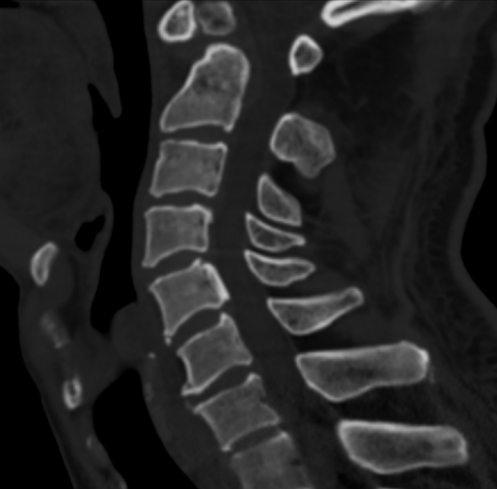

寰枢椎脱位ct图

寰枢关节脱位

难复性寰枢椎脱位1例

寰枢关节脱位的影像诊断

病例点评寰枢椎脱位1例